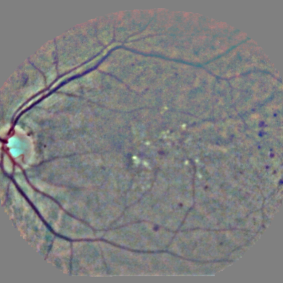

5.4 Visualization Artifacts

Artifacts from various visualization algorithms are illustrated in Fig. 4. First, it can be seen that the original sensitivity criterion is inadequate to finely detect lesions. Sensitivity maps seem to indicate that if lesions grew in size, the diagnosis would be consolidated. The hue constraint prevents the lesion detections from growing. Second, it can be seen that, due to the drafting effect, blood vessels (lesion confounders) in the vicinity of lesions are detected, both in the hue-constrained sensitivity maps and in the layer-wise relevance propagation maps. The resulting false detections are not necessarily connected to the true detection, so they cannot be removed easily through image post-processing techniques: they have to be removed beforehand, hence the proposed approach.

The performance of the proposed pixel-level detector, using ‘net B’, is illustrated in Fig. 9 and 10 on two images from independent datasets. The first image comes from the publicly-available Messidor dataset999http://www.adcis.net/en/Download-Third-Party/Messidor.html. The second image comes from a private dataset acquired with a low-cost handheld retinograph (Quellec et al., 2016a).

Three ConvNets were trained to detect referable DR in the Kaggle-train dataset, using the proposed heatmap optimization procedure. Then, we evaluated how well those ConvNets could detect lesions in the DiaretDB1 dataset, without retraining them. For lesion detection at the image level, they outperformed previous algorithms, which were explicitly trained to detect the target lesions, with pixel-level supervision (see Fig. 7). This superiority was observed for all lesions or groups of lesions, with the exception of ‘red lesions’. Experiments were also performed at the lesion level: for all lesion types, the proposed algorithm was found to outperform recent heatmap generation algorithms (see Table 3). As illustrated in two examples (see Fig. 9 and 10), the produced heatmaps are of very good quality. In particular, the false alarms detected on the vessels, in the vicinity of true lesions in the unoptimized heatmaps ( maps), are strongly reduced with sparsity maximization (, , ). These experiments validate the relevance of image-level supervision for lesion detectors, but stress the need to optimize the heatmaps, as proposed in this paper. Note that detection performance is not affected much by image quality: very good detections are produced in the blurry image obtained with a low-cost, handheld retinograph (see Fig. 10). This is a very important feature, which opens the way to automated mobile screening. However, it can be observed that the ‘AlexNet’ architecture, which achieves moderate DR detection results, also achieves poor detection results at the lesion level, even after heatmap optimization (see Table 3): to ensure good detection performance at the lesion level, the proposed optimization framework should be applied to ConvNet architectures that achieve good image-level performance.